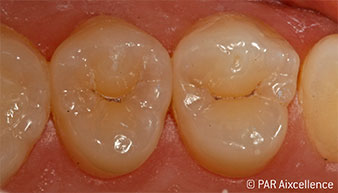

Abb 1: Ausgangsbild der Zähne ohne scheinbare klinische Karies.

Abb 9: Abgeschlossene, langlebige Restaurationen.